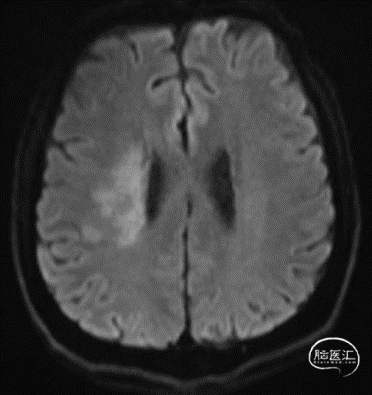

DWI:右侧基底节区多发急性梗塞灶。

颅脑DWI:右侧脑室旁及基底节区梗塞灶(亚急性期)。

颅脑DWI:左侧基底节、枕顶叶及放射冠区急性梗塞灶。